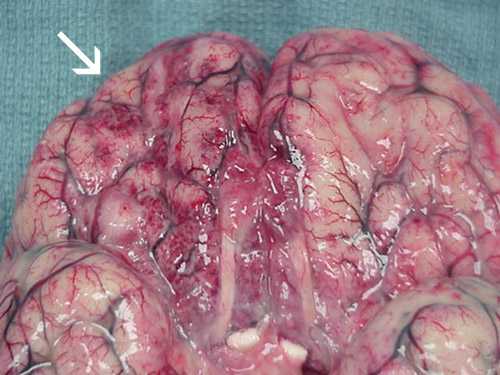

Photos of Naegleria fowleri

These photos of Naegleria fowleri in a variety of forms are presented to aid in laboratory diagnosis. Please be aware that these photographs are intended to aid in laboratory diagnosis and may be disturbing to some viewers.